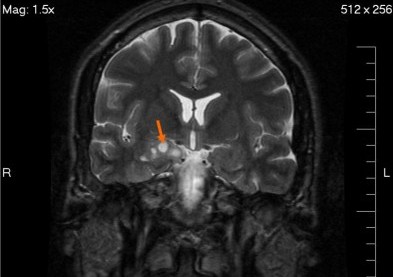

Une tumeur au cerveau dépistée grâce à une optométriste

Un examen des yeux chez un optométriste (dans les pays ou la profession est réglementée, en France chez un ophtalmologiste) peut non seulement sauver la vue, mais aussi la vie ! En effet, c’est grâce à un examen des yeux chez une optométriste qu’une fillette britannique de 12 ans a pu guérir d’une tumeur au cerveau. La jeune Lucy se plaignait de sensations de fatigue et de soucis d’équilibre depuis plusieurs mois.  Ce n’est que lorsque sa vision a commencé à devenir trouble que la tumeur causant à Lucy ces symptômes a été décelée par l’optométriste qui a décelé une tache anormale sur la rétine. Elle a immédiatement recommandé de se rendre à l’hôpital pour des examens médicaux plus approfondis.

Un scanner effectué à l’hôpital de Coventry a révélé la gravité de la tumeur puis Lucy a été emmenée d’urgence à l’hôpital pour enfants de Birmingham. L’opération pour retirer la tumeur s’est bien déroulée : la jeune fille n’est encore complètement hors de danger mais les risques sont déjà bien plus bas depuis cette intervention.  Il ne reste plus quà souhaiter à Lucy une prompte guérison !